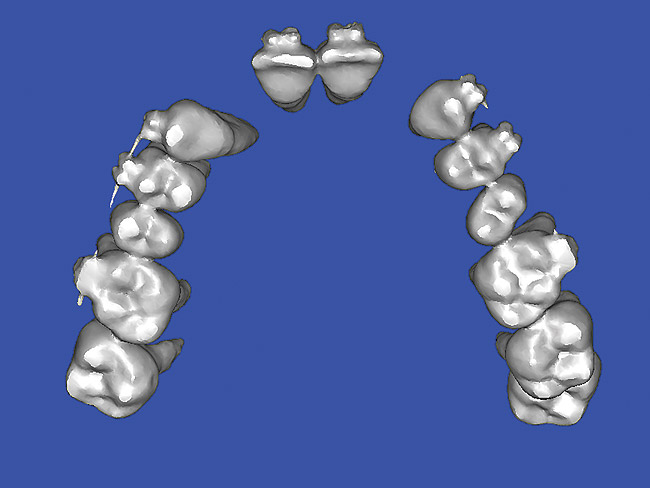

Figure 10  SOFTWARE IMAGING By slicing the maxilla axially, the images revealed the differing morphology of the central incisors, canines, premolar, and molar roots.

Figure 10

The CT axial views represent an important instrument in gaining a better understanding of anatomical features that cannot be determined by any other imaging modality (Figure 10). When the maxilla is sliced axially at the level where the roots meet the crest of the bone, the adjacent and surrounding root morphology can be revealed. Of note are the individual and different shapes of each of the central incisors, canines, premolars, and molar roots. These images reflect a phenomenon defined by the author as the “restorative dilemma.” Clinicians encounter this often difficult dilemma when attempting to re-establish morphologically correct emergence profiles in prosthetic teeth as they ascend from the round shape of the implant(s). When planning for the placement of the implant in the left lateral incisor area, there appeared to be adequate mesial-distal space between roots as seen in the axial view of Figure 11. A closer inspection of the planned site for the right lateral incisor revealed a more narrow space, further complicated by the distal rotation of the palatal aspect of the tooth root. Based on this preliminary position, the 3.75-mm diameter, straight-walled implant can be seen encroaching on the lamina dura periodontal ligament space of the right canine and central incisor. If there was not adequate room for this diameter and type of implant, the adjacent teeth could sustain potential iatrogenic damage. Therefore, additional “tweaking” of the virtual placement was necessary to diminish this risk.